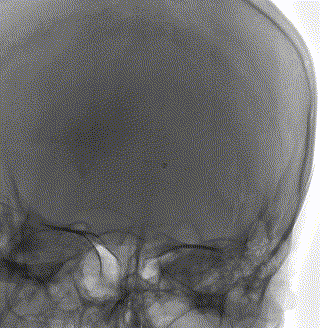

股动脉入路动脉造影显示上矢状窦后部和左侧横窦不显影,静脉期显影延迟,皮层静脉开放并明显增粗; 股静脉入路超选颅内静脉,微导丝和微导管引导ACE抽吸导管超选颅内静脉窦造影显示上矢状窦后部和左侧横窦内血栓影。

ACE抽吸导管到位后撤出微导丝和微导管,开启负压泵,轻轻推拉ACE抽吸导管,使导管头端在血栓内缓慢往复移动,重复上述操作。